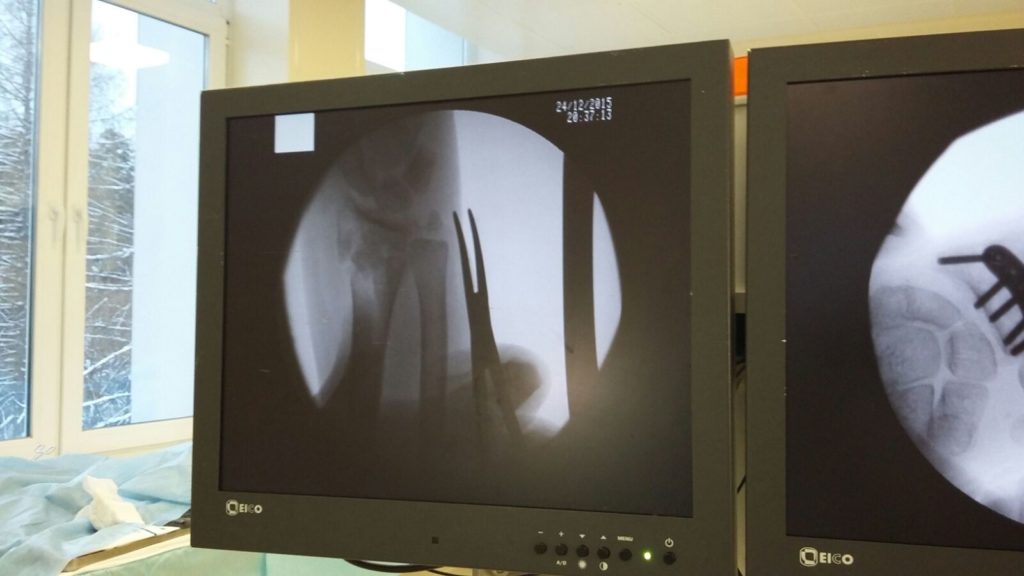

Операция - открытая репозиция, остеосинтез лучевой кости пластиной с костной ксенопластикой материалом "Остеоматрикс". На контрольных снимках в три месяца имеется консолидация перелома, миграции фиксатора нет, имеется остеоинтеграция ксенопластического материала.

Отдаленные результаты через 3 (три) месяца: